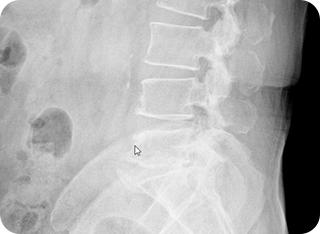

환자 증상, 증후 진단 및 X-ray 검사

우리가 흔히 아는 기본적인 검사는 환자의 병력 · 증상 · 신경학적 검사, 이학적 검사 그리고 척추의 배열 상태를 보는 역동적 방사선 촬영입니다. X-ray 검사는 척추 뼈, 디스크를 포함한 관절 부분의 퇴행 정도, 척추의 측만증이나 후만증 여부, 그리고 실제 굴곡과 신전시 척추의 불안정성을 진단하는데 있어서 매우 중요한 검사입니다.